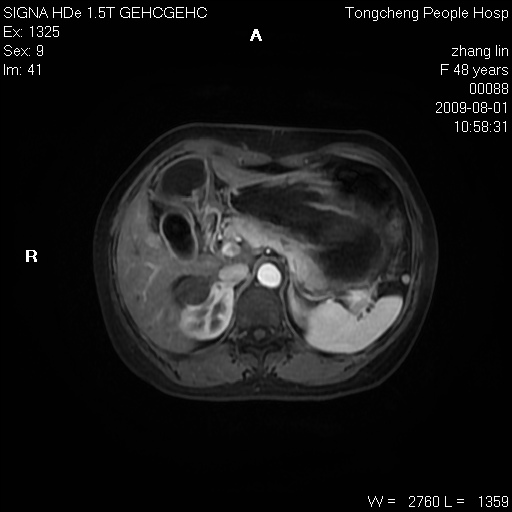

女,48岁。健康体检,彩超发现右肾占位性病变。平素健康。

临床诊断:右肾占位性病变,性质待定(囊肿?肿瘤?)。

上中腹部mr平扫+增强扫描,图像如下:

右肾上极见一类圆形病灶,t1wi呈等信号t2wi呈等高混杂信号,三期增强无强化,边界清---考虑囊肿出血。

同反相位均表现为等信号,病变无强化,考虑含蛋白的囊肿可能,弥散加权相或许有些帮助,

慢性胆囊炎